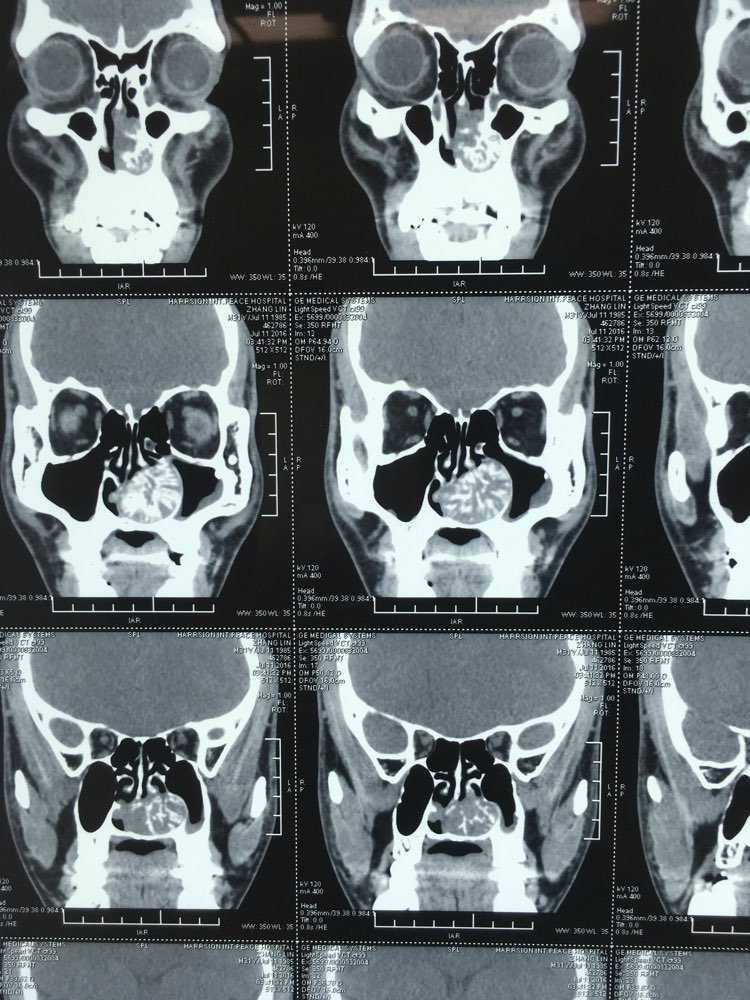

【原创】冠状位鼻窦ct解剖 - 耳鼻咽喉头颈外科 - 专业医生社区,医学,

鼻窦炎7年,,做完ct检查后大夫说要手术,请问这个情况手术难度大吗?风

鼻窦ct - 医学影像学讨论版 - 爱爱医医学论坛